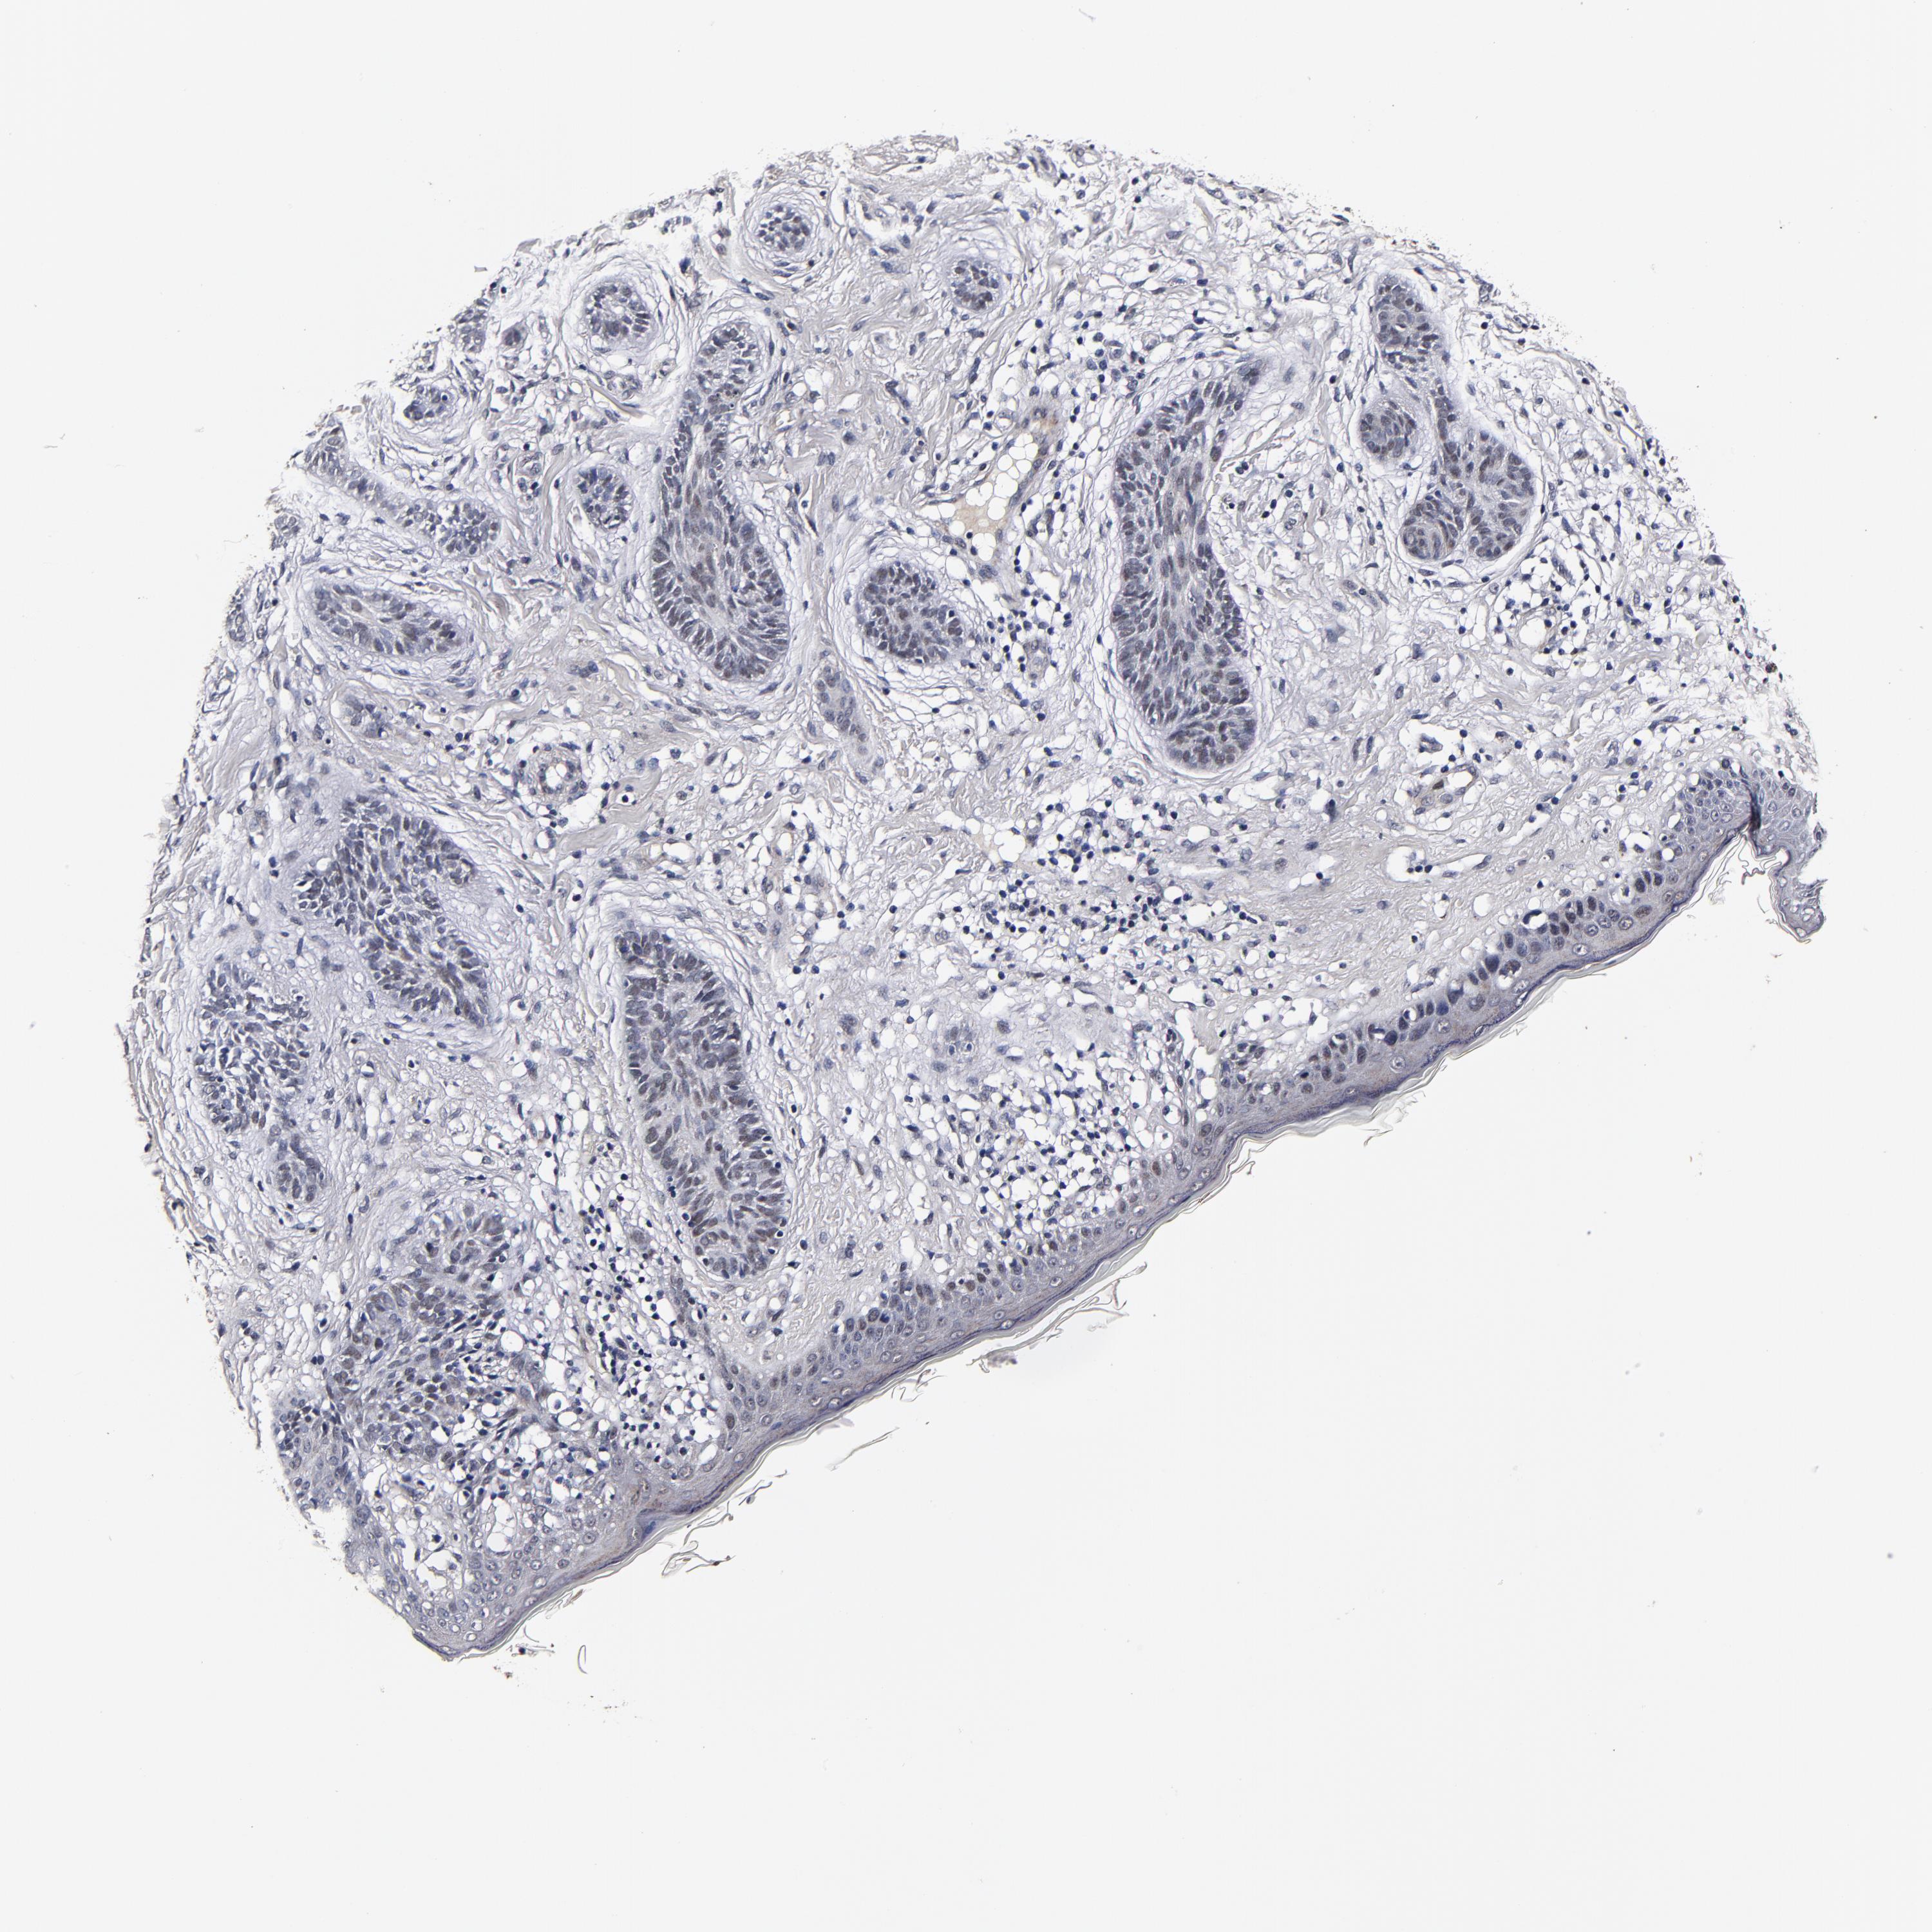

SKIN CANCER - Protein expressioni

A mouse-over function shows sample information and annotation data. Click on an image to view it in a full screen mode. Samples can be filtered based on level of antibody staining by selecting one or several of the following categories: high, medium, low and not detected. The assay and annotation is described here.

Antibody stainingi

Antibody staining in the annotated cell types in the current human tissue is reported as not detected, low, medium, or high, based on conventional immunohistochemistry profiling in selected tissues. This score is based on the combination of the staining intensity and fraction of stained cells.

Each image is clickable and will lead to virtual microscopy that enables deeper exploration of all samples and also displays staining intensity scores, fraction scores and subcellular localization as well as patient and tissue information for each sample.

Antibody HPA040390

Antibody CAB002611

Staining

High

Medium

Low

Not detected

Intensity

Strong

Moderate

Weak

Negative

Quantity

>75%

75%-25%

<25%

None

Location

Nuclear

Cytoplasmic/membranous

Cytoplasmic/membranous,nuclear

Squamous cell carcinoma, NOS